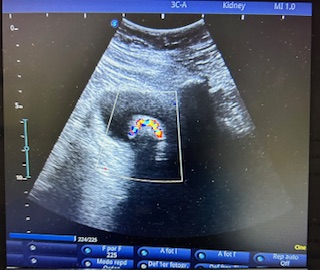

Hallazgos ecográficos

Decidimos realizar ecografía vista la exploracion realizada. En la misma consulta, con ayuda del ecógrafo vislumbramos las paredes vesicales lisas y ecogénicas con la luz anecogénica conteniendo una imagen hiperecogénica con sombra acústica posterior que nos impresionaba de una litiasis vesical. Aplicando el Doppler (imagen clave) se apreciaba pequeña captación de color posterior a la imagen indicativa de litiasis, denominada centelleo. Además, se descartó hidronefrosis y se vislumbró un correcto flujo en unión uretero-vesical descartándose posible obstrucción.